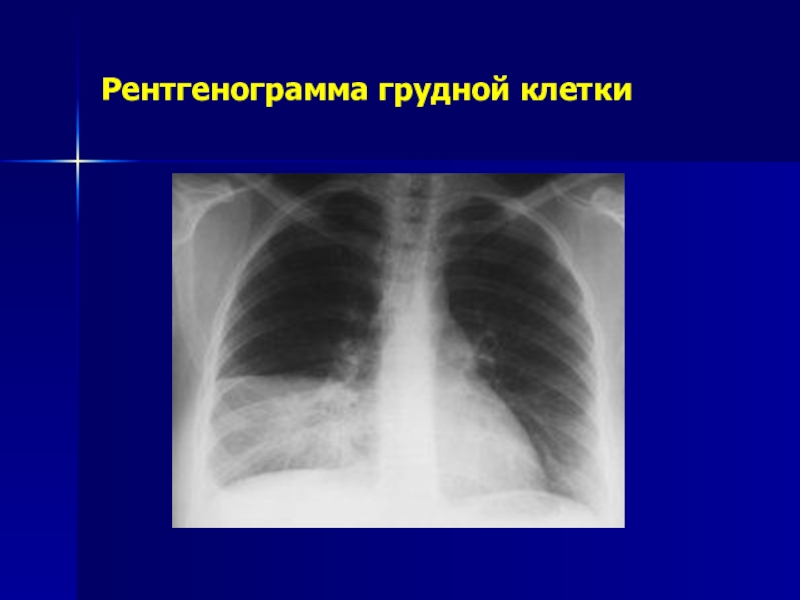

Слайд 26Рентгенограмма грудной клетки

Рентгенограмма грудной клетки